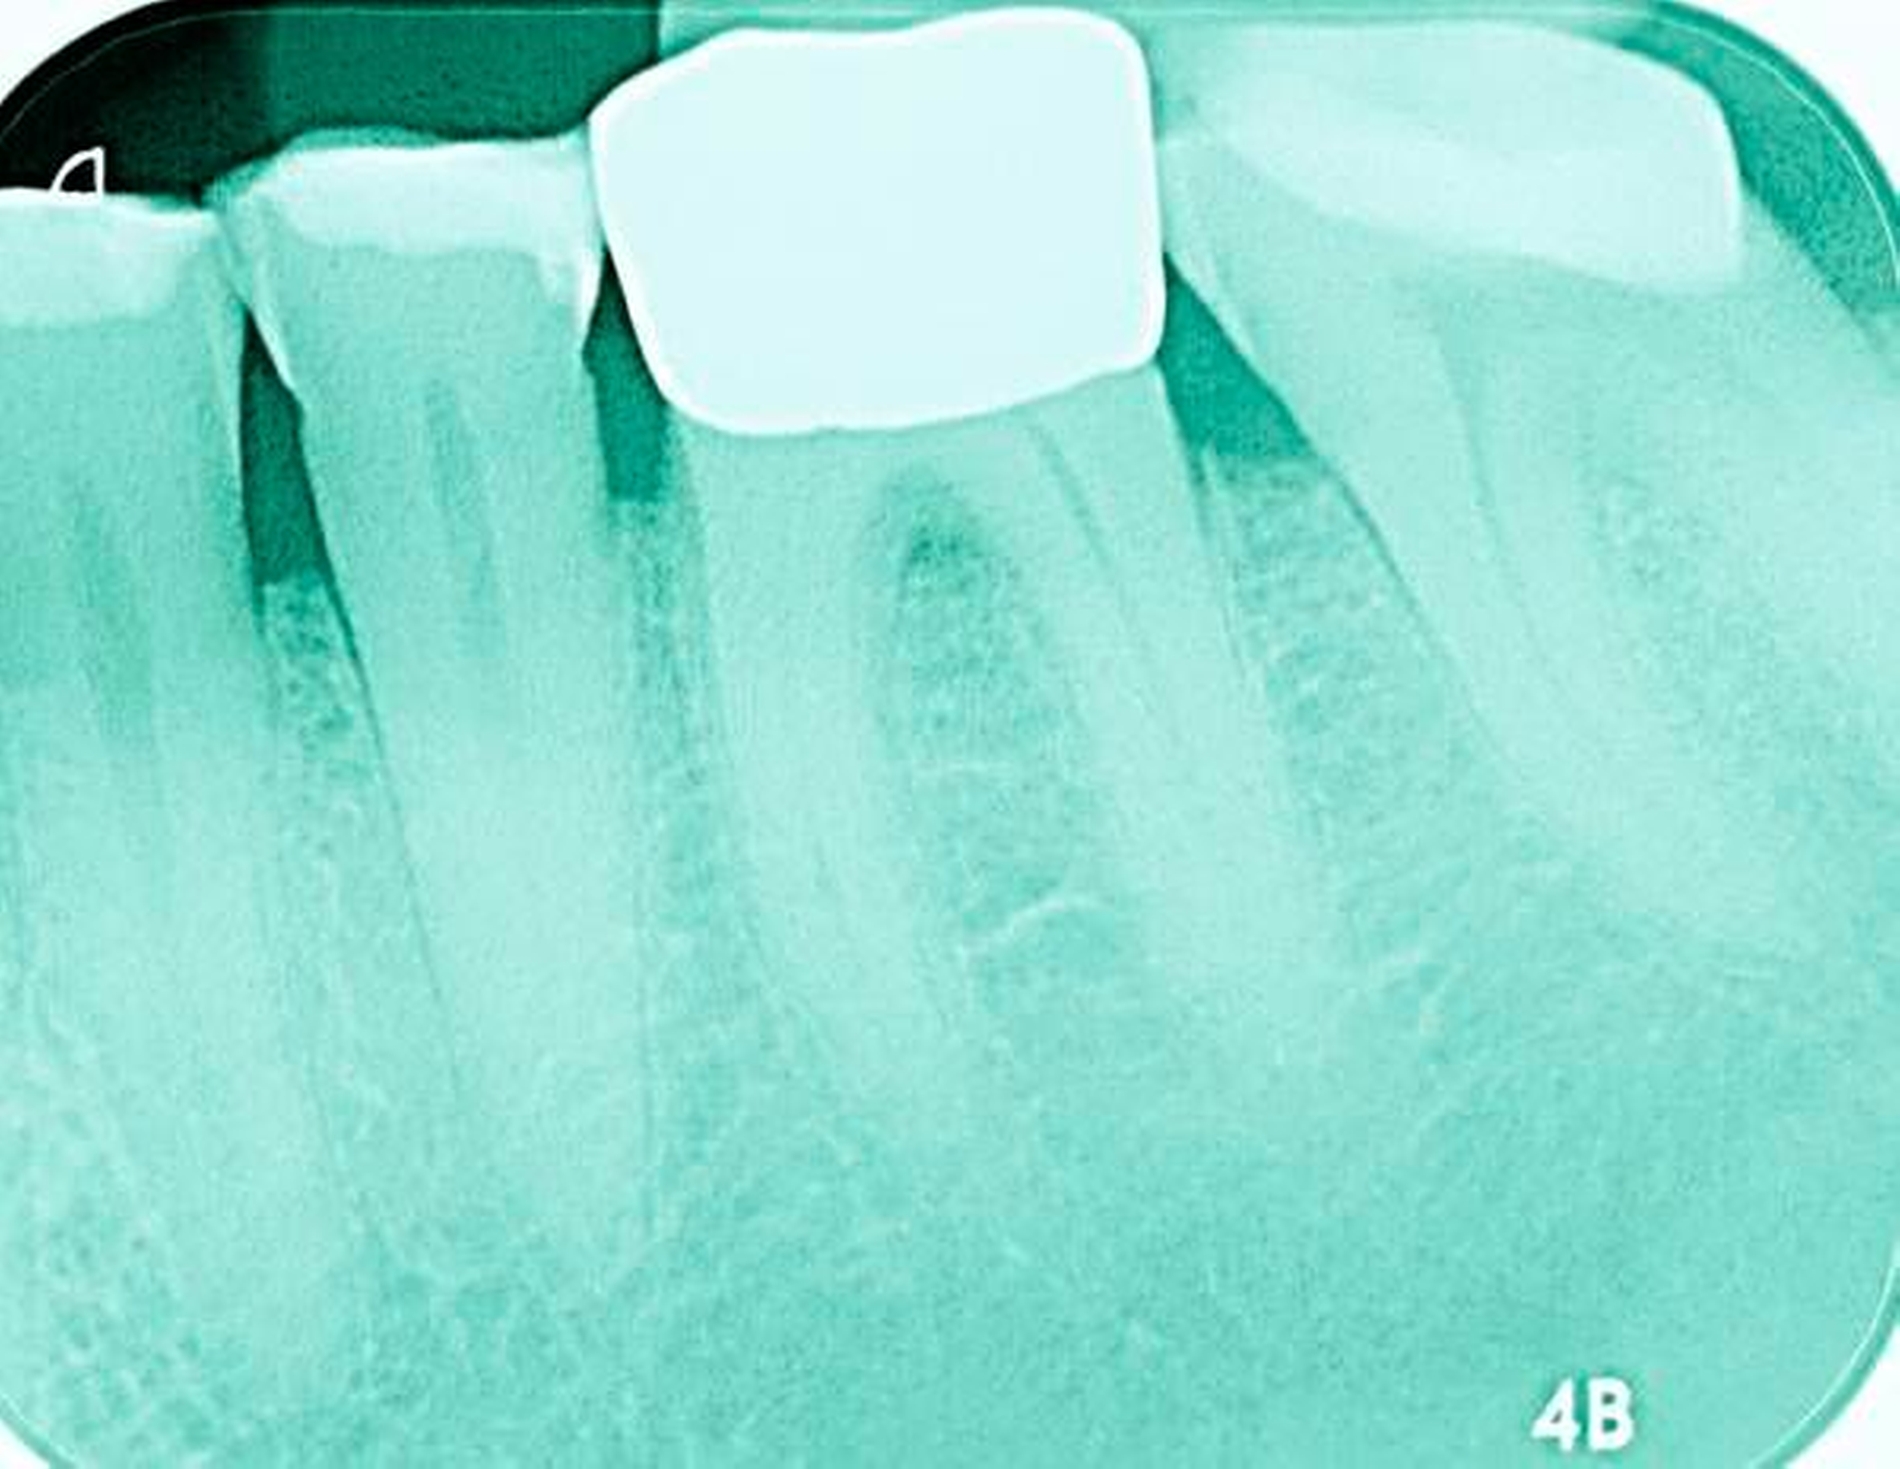

Abbildung 4: Anliegen eines 76,5-jährigen Patienten (Anfrage per E-Mail). Zitat: „Mich plagt eine … Entzündung des Mundraums, die auch das Zahnfleisch meiner Zahnstummel angreift, weshalb ich nur noch Breiartiges zu essen vermag. Ein Angsthase wie ich geht zum Zahnarzt NUR unter dem Eindruck akuter Schmerzen!“

Damit wird die Hygienefähigkeit zumindest partiell verbessert und Spielraum für künftige Planungen und Vorgehensweisen unter besseren Bedingungen belassen. Das Procedere ist in den Abbildungen 4 und 5 beschrieben. Bei dem in Abbildung 4 vorgestellten Patienten lag eine Oralphobie im Seniorenalter vor. Die Verlaufsbeschreibung macht deutlich, dass selbst im fortgeschrittenen Alter eine Adaptation an zahnärztliche Interventionen im Einzelfall noch möglich ist.

4. Vorgehen bei frakturierten Zahnkronen/Wurzelresten

Üblicherweise werden frakturierte Zahnkronen beziehungsweise Wurzelreste restaurativ wieder aufgebaut oder es erfolgt eine Extraktion. Im Seniorenalter erscheint es hingegen manchmal als Kompromissmaßnahme vertretbar, Wurzelreste vorerst zu belassen und etwa mit adhäsiv eingebrachtem Komposit knapp über Gingivahöhe abzudecken. Dies bietet sich vor allem dann an, wenn die Wurzelkanäle bereits obliteriert und endodontische Interventionen nicht erforderlich sind (Tabelle 4) [Staehle et al., 2017].